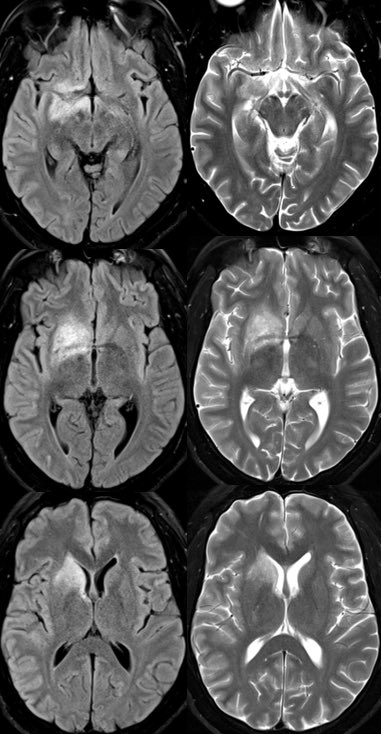

What is the most likely diagnosis in this 30 y/o M presenting w/ a few weeks of headaches, photophobia, vision loss, confusion, and ataxia?

Answer: MOG antibody-associated disease (MOG-AAD)

Path: MOG-AAD is an autoimmune inflammatory demyelinating disease targeting oligodendrocytes (NMO targets AQP4)

▶️SPINE findings: preferentially affects the lower cord, particularly the conus

▶️Patterns may be longitudinally extensive or short segment

▶️Spinal gray matter involvement can appear as thin linear T2 signal abnormality on sagittal or appear as on H on axial “H sign”

4️⃣Brain findings occur in <50% and may be ADEM or CLIPPERS-like with typical involvement of deep gray and posterior fossa

5️⃣Spinal cord involvement tends is less often LETM and affects the lower thoracic cord and conus